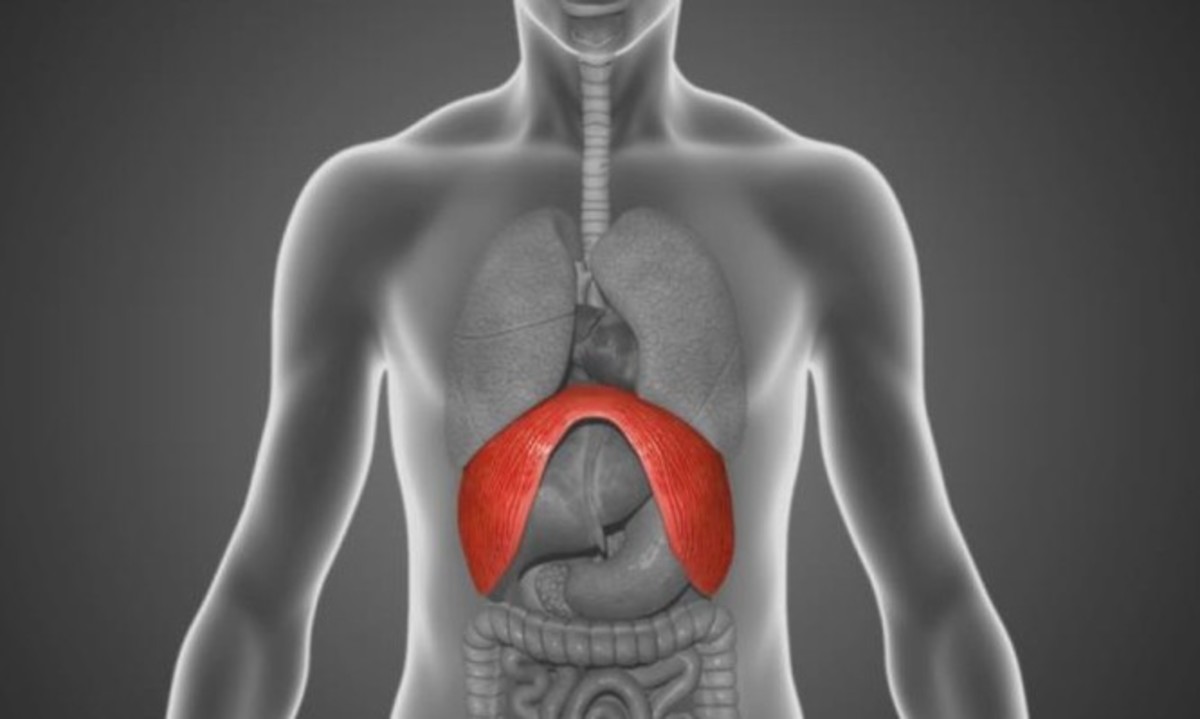

Για να σταματήσει ο λόξιγκας υπάρχει μια μέθοδος που κάνει το σώμα να κατακρατά στιγμιαία διοξείδιο του άνθρακα, το οποίο πιστεύεται ότι χαλαρώνει το διάφραγμα και σταματάει τους σπασμούς που προκαλεί το λόξιγκα.